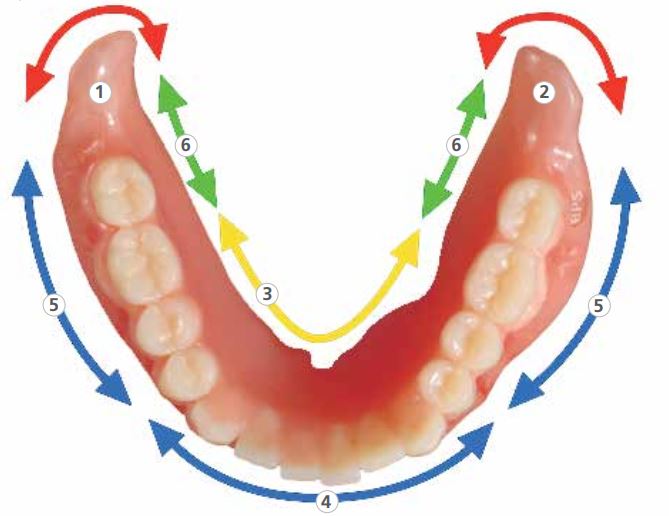

2. Cơ chế hít dính của hàm giả hàm dưới

Điều kiện tiên quyết để đạt được hiệu quả hít dính ở hàm dưới là phải có hiểu biết toàn diện về cơ chế hít dính.